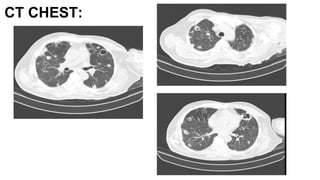

CT CHEST:

Ct chest

• Multiple varying size cavitatory lesions along with areas of

consolidation involving both lungs

• Left subscapular and Deltoid abcess , sclerosis of humerus

head

S/o

• Multiple septic emboli i/v/o abscess in the left shoulder

D/D:

• Cavitatory metastasis

• Vasculitis are less likely

Fibrotic strands and interstitial thickening seen involving both

the lungs - represent sequelae of prior infection